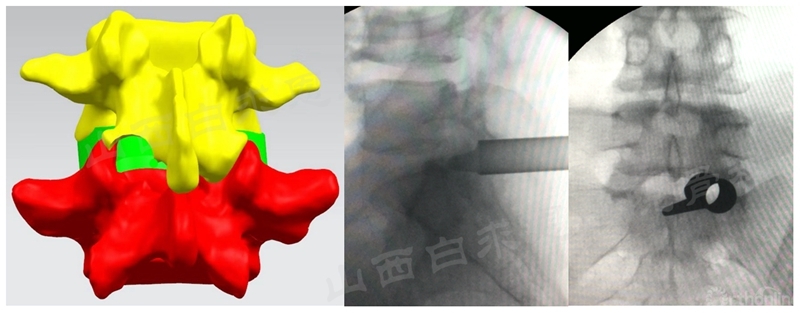

(4)上关节突成形

N:Nerve root(神经根);Disc(椎间盘)

(5)椎间盘切除和终板处理

(6)椎间植骨和融合